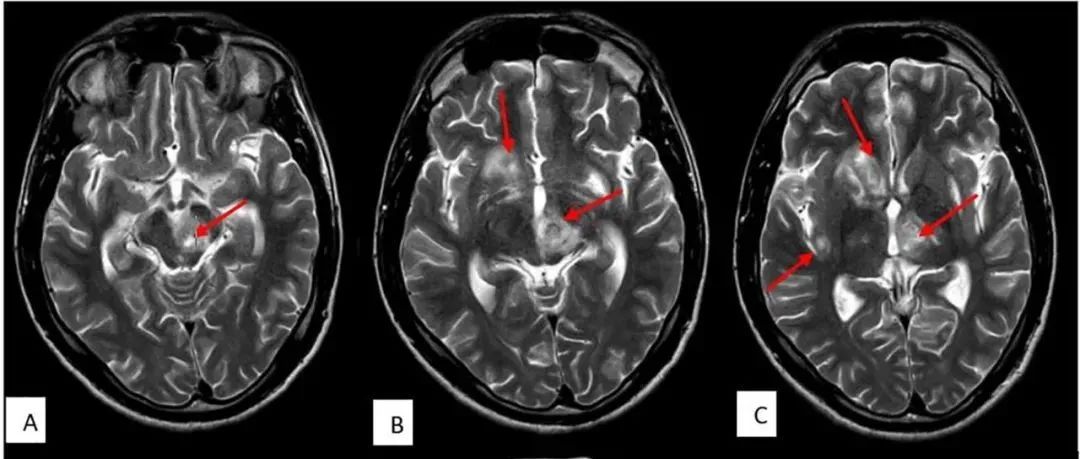

35岁女性,在2次右手局灶性感觉性发作后至医院就诊,其中第2次发展为全面性强直阵挛发作。查体未发现运动或感觉缺陷。MRI可见显示5个幕上病变,最大的2个为囊性病变——左侧中央后回上外侧30×30×32mm和右侧中央后回外侧7×9×6mm。所有病变均为T1低信号和T2高信号,周围有轻度血管源性水肿(图1A和C)。2个囊性病变呈周围强化、FLAIR高信号,且没有弥散限制(见图1B和D)。(图:MRI可见显示5个幕上病变,最大的2个为囊性病变——左侧中央后回上外侧30×30×32mm和右侧中央后回外侧7×9×6mm[A-D];病变呈T1低信号[A]和T2高信号,周围有轻度血管源性水肿[C];其在FLAIR上呈高信号[C],周围中度强化[B],无弥散受限[D];左侧中央后回上外侧病灶活检组织病理学显示脱髓鞘伴有囊性变和明显的星形胶质细胞增生[E],血管周围淋巴细胞成套[F],无残留髓鞘[G],CD163+巨噬细胞[H],以及大量反应性星形胶质细胞[I])...